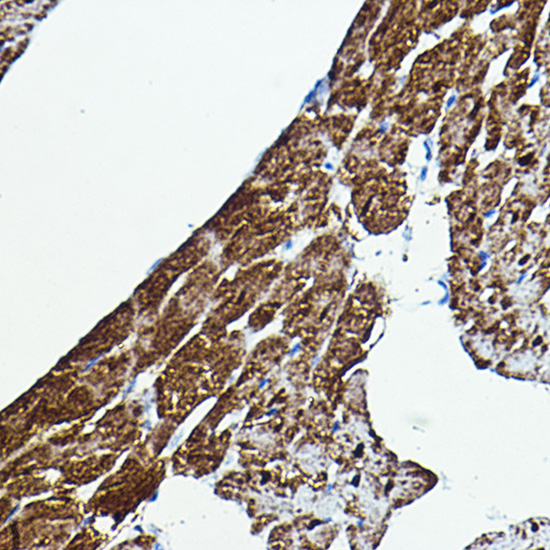

Immunohistochemistry of paraffin-embedded rat heart using B-Raf Rabbit pAb.